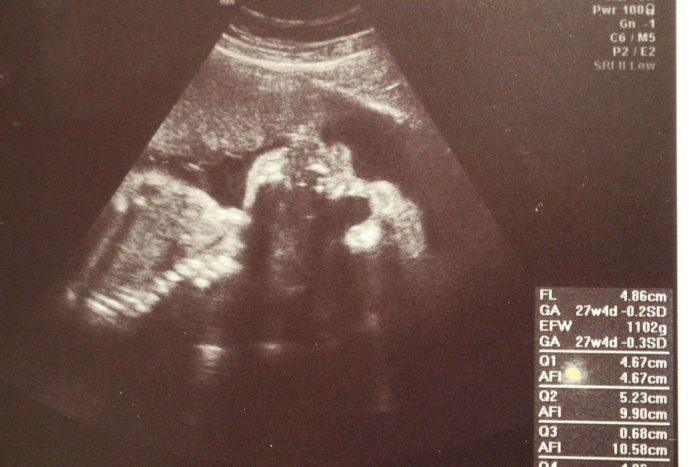

チャーミー小結さんの妊娠27週目のエコー写真

管理入院中は、ずっとベッドで安静第一に過ごさねばなりませんが、毎日看護師さんが赤ちゃんの心音を確認してくれるので安心でした。